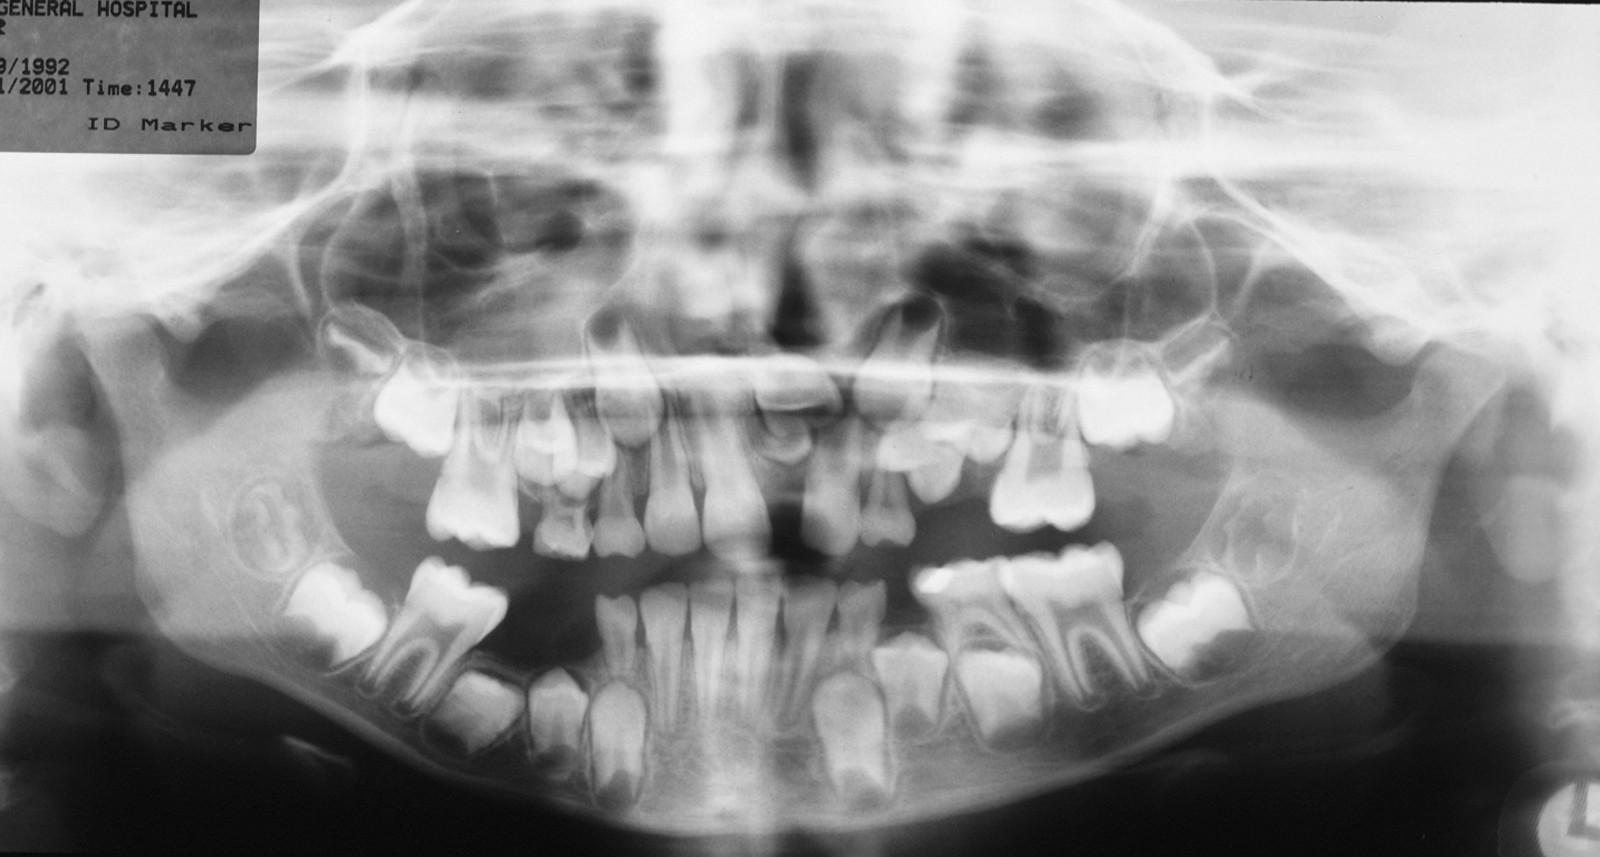

Injury to the inferior alveolar nerve is less common but harder to manage. The nerve may be directly injured by the needle during the injection of local anaesthetic or may be crushed by the tooth root during elevation. Rarely the roots of the tooth may surround and encase the nerve so that elevation is unavoidable. Clues to this injury can be seen on the radiograph and when the tooth will not elevate easily (it actually feels as if it is attached by a rubber band).

Increasing availability of cone beam computed tomography scans (CBCT) can be useful in assessing lower third molars whose roots are in close proximity to the inferior alveolar nerve and helping to determine the risk of neurosensory disturbance. If such cases are identified, a decision may be made to remove the crown of the tooth only (coronectomy; see above).